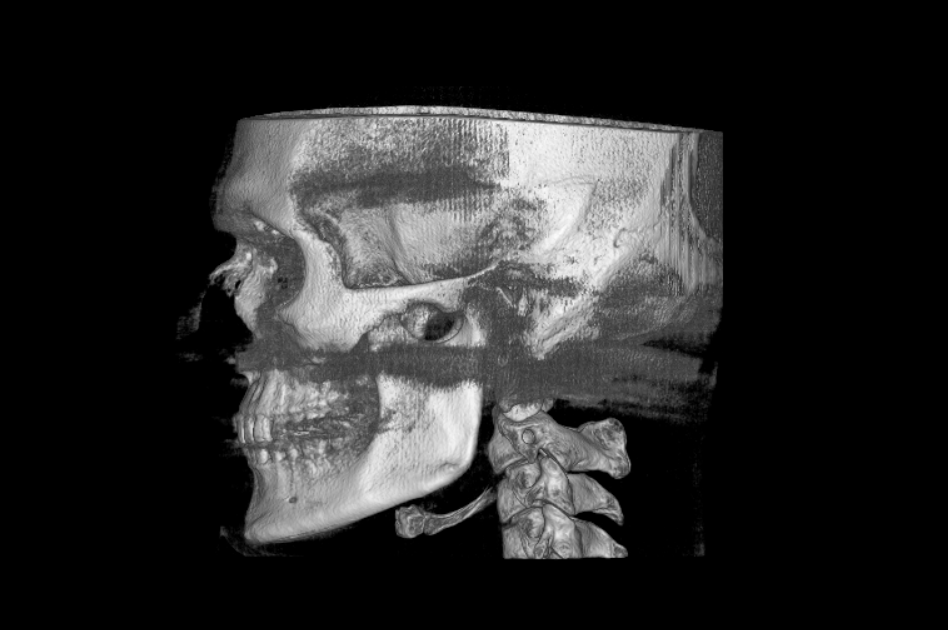

I’m wondering whether a genioplasty would be sufficient for me. My teeth are perfectly aligned, I have no breathing problems, and my only concern is a weak chin. I would like to achieve more width, projection, and some vertical height.